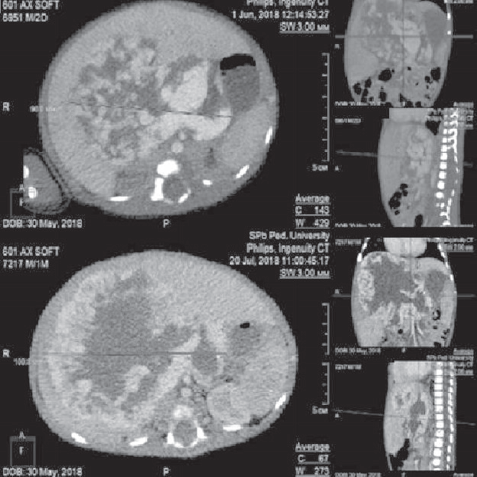

Проведено обследование: УЗИ органов брюшной полости — визуализируется объемное образование с кровотоком, занимающее всю правую долю печени. МСКТ брюшной полости с контрастным усилением — выявлено гигантское сосудистое образование печени срединного расположения (рис. 8).

Рис. 8. Аксиальные компьютерно-томографические снимки во все фазы контрастирования

Fig. 8. Axial CT images in all phases of contrast

При контрольном обследовании в возрасте 3 мес. на УЗИ признаков прогрессирования образования печени не выявлено. МСКТ органов грудной клетки и брюшной полости с в/в контрастированием: в легких без очаговых и инфильтративных изменений, отмечается умеренное уменьшение объема образования, уменьшение диаметра и количества сосудов в центральных отделах образования (рис. 9).

Рис. 9. Компьютерно-томографические снимки брюшной полости в различных плоскостях и фазах контрастирования, контроль в 3 месяца

Fig. 9. CT images in various planes and contrast phases, control at 3 months

При контрольном обследовании в возрасте 8 мес. по МСКТ отмечается продолженное уменьшение размеров образования на 65 % от первичного объема.